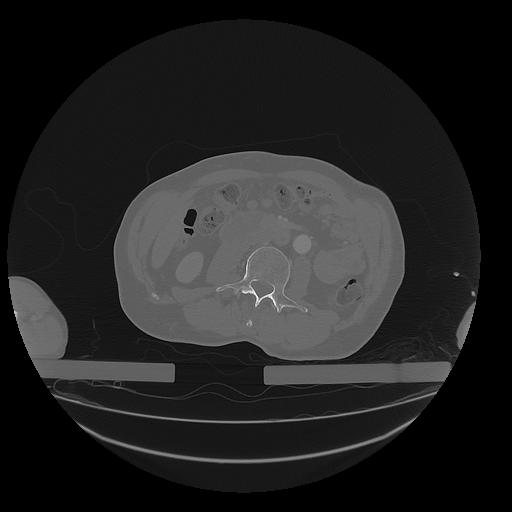

31 PULMON,CE,Vol,1.0,PULMON,,